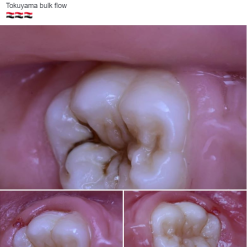

Anterior Case

Courtesy of Dr A. Mak, Australia

Posterior Case

Courtesy of Dr R. Asparuhov, Bulgaria